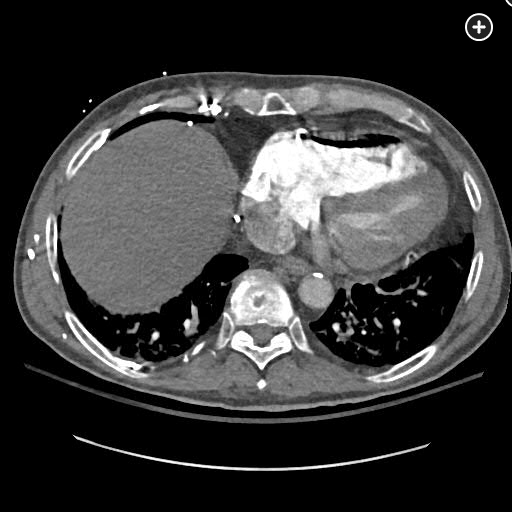

The CT pulmonary angiogram demonstrates a large volume of air in the right atrium, ventricle, and pulmonary outflow tract, with leftward bowing of the interventricular septum, suggestive of acute right heart strain (Figure 1, Figure 2, Figure 3, Figure 4).

CT image demonstrating air in the right ventricle with leftward bowing of the interventricular septum, indicative of acute right heart strain.